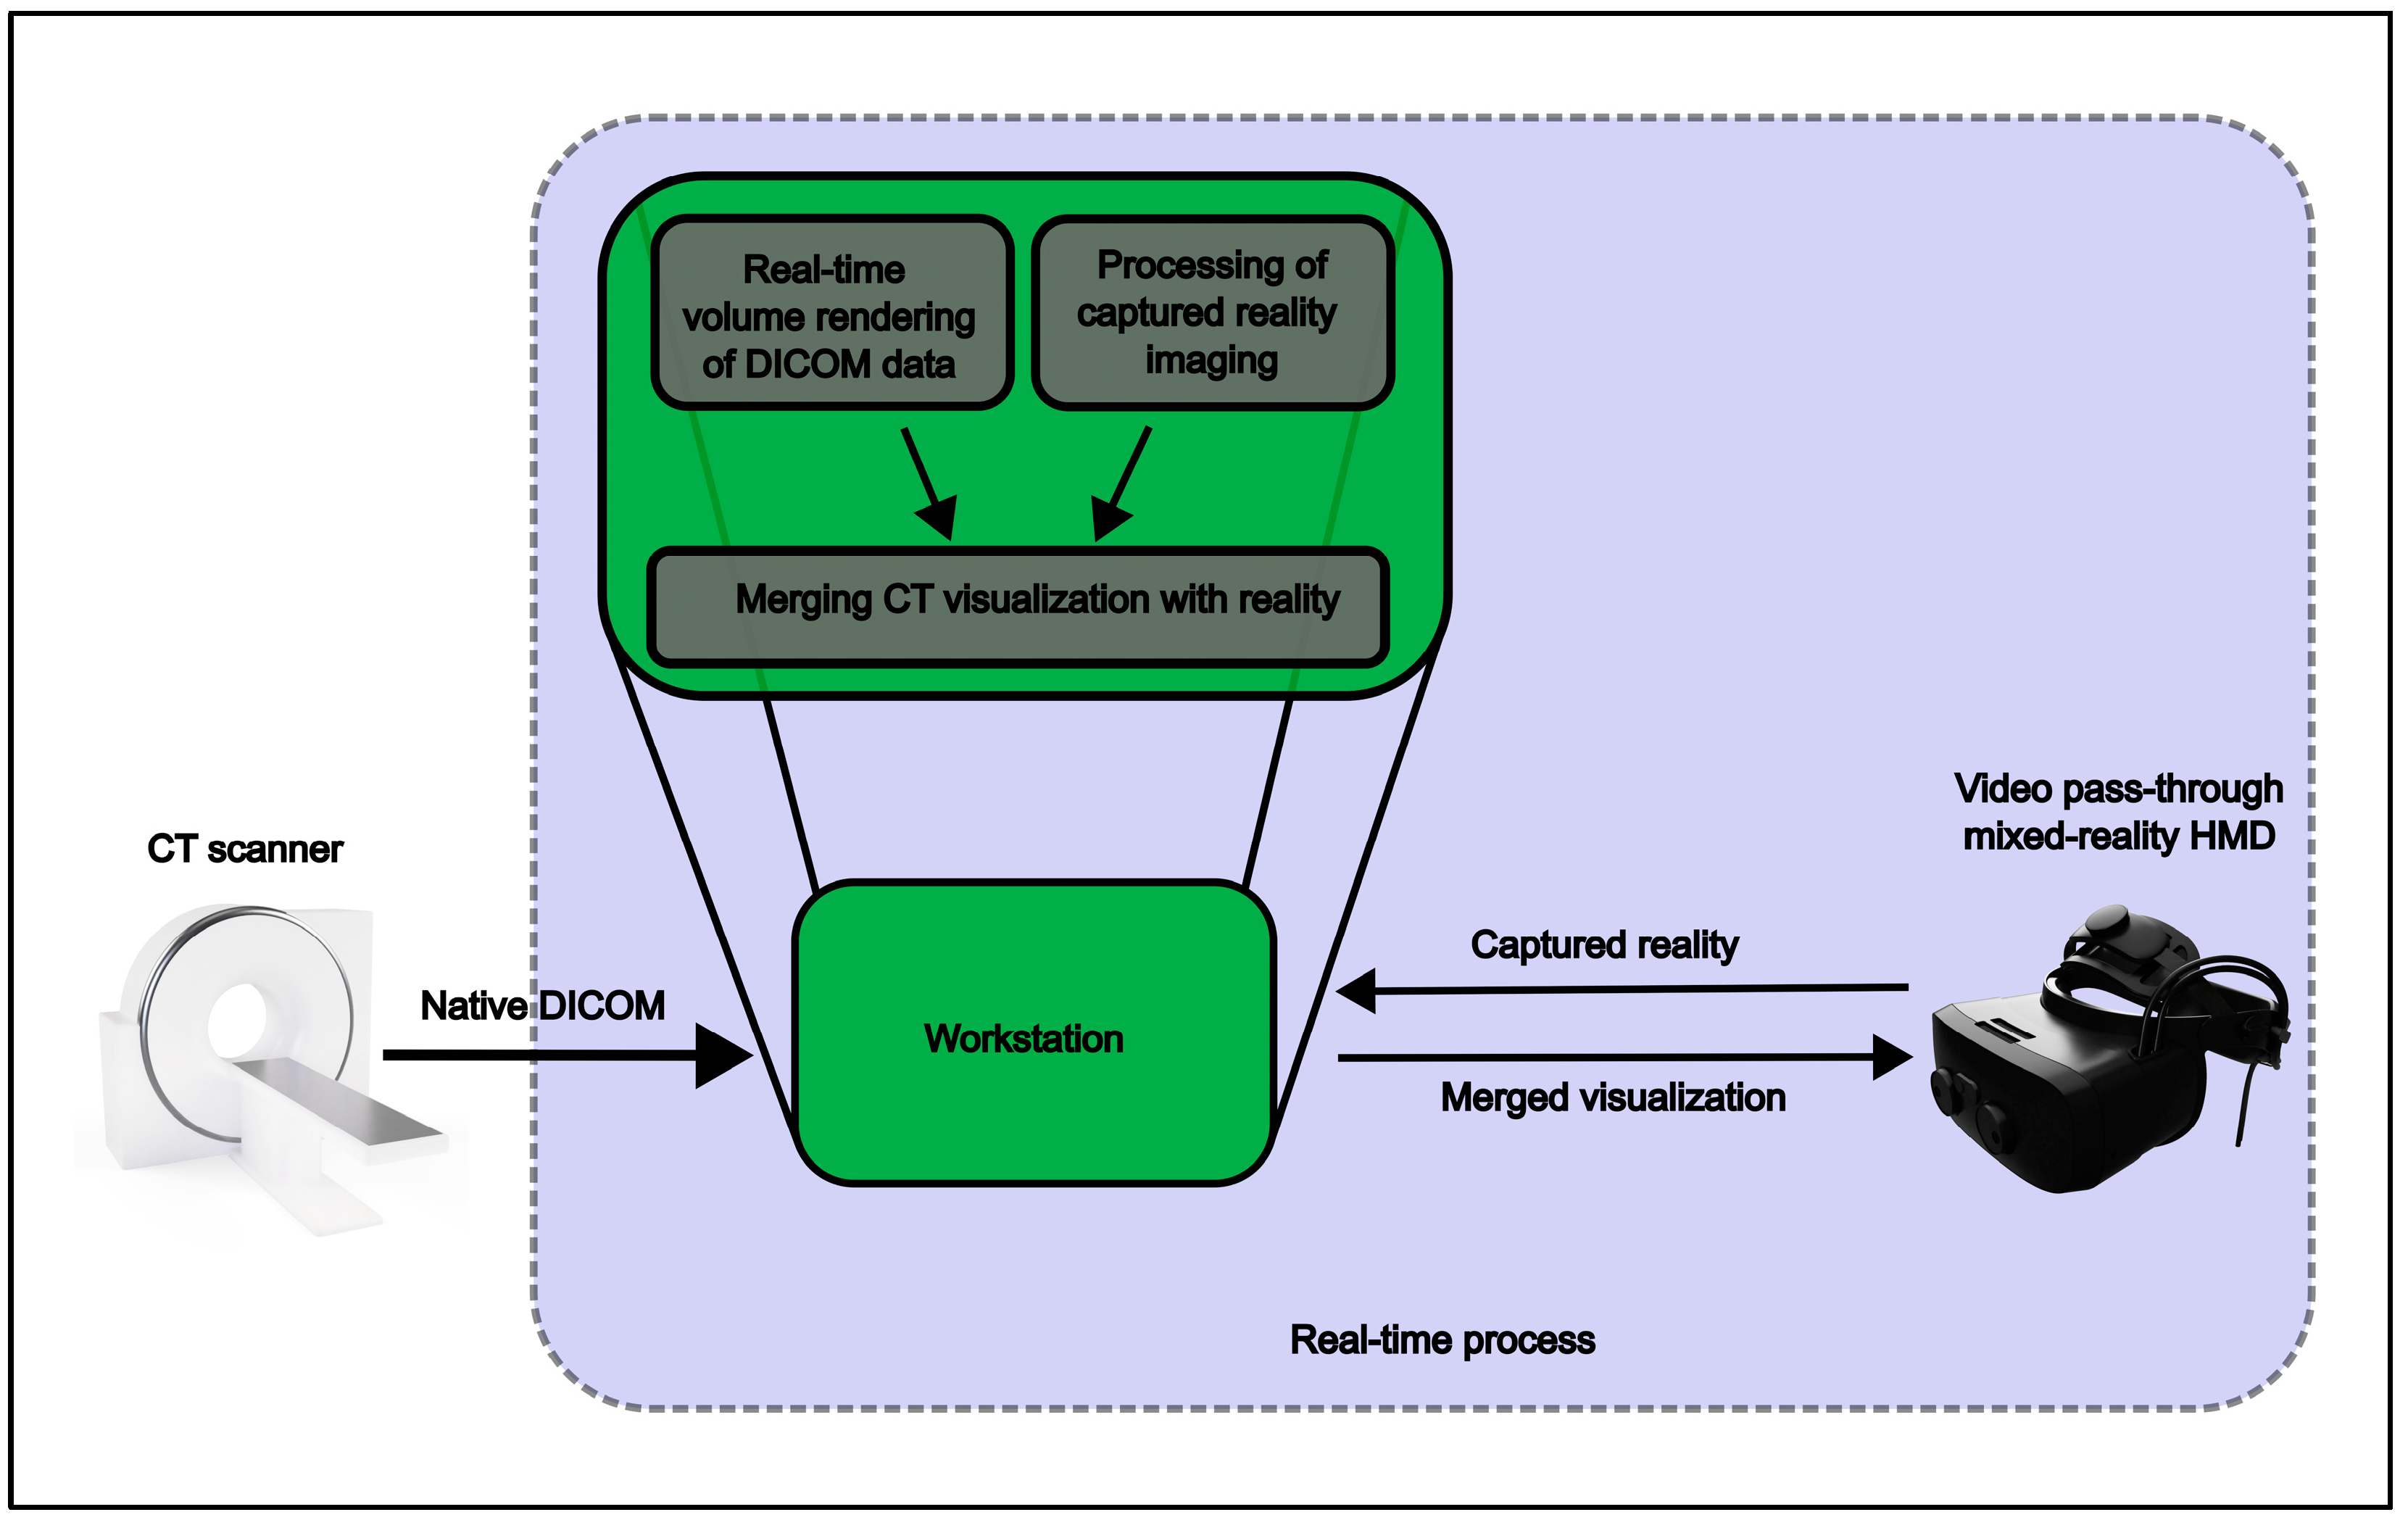

Figure 1 illustrates the data flow of the system, highlighting the real-time process of workstation-based volume rendering and incorporating the pass-through stream. Visualization of the reconstructed CT image data was adapted through tissue windowing, color grading, and cropping to expose the region of interest (e.g., tumor mass and/or vascular system). Hounsfield coupled windowing and color grading were variably adjusted by visual feedback of the displayed dataset. Adjusted visualization was saved as a reproducible preset. All examiners were previously trained in operating the controllers, general software functions, and editing tools. Each case was examined by two surgeons, each with a minimum experience of 4 years in the field of thoracic surgery. One surgeon operated the tools in the MR environment, while the other observed and assisted through a 2D stream displayed on the workstation’s monitor.

Figure 2 illustrates the examination setup in a third-person view, simulating the examiner’s holographic vision of CT data.

Real-time reconstructed high-resolution thoracic CT scans were used in three oncological cases of male patients, two presenting with large tumor masses inside the chest and one presenting with a potentially malignant lesion of the 7th rib of the right dorsal hemithorax. There were no oncologic conditions in the previous history of all three patients. A landmark-adjusted overlay was initiated by windowing the reconstructed pixel cloud to display the patient’s skin surface, as can be seen in

Figure 1. The regions of interest were then pointed out using the integrated tools for tissue filtering, color grading, and opacity adjustments.